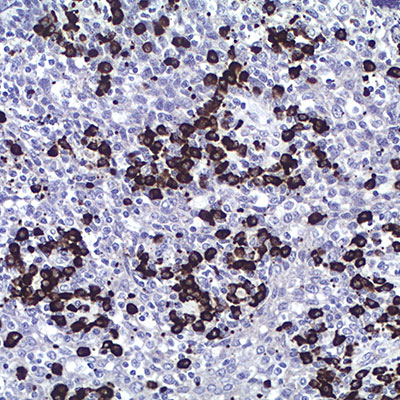

Kappa Light Chain

Este kit está diseñado para el estudio de monoclonalidad de cadenas ligeras Kappa en los tumores linfoides, mieloides y en otros Síndromes Linfoproliferativos, sobre secciones de tejidos humanos fijados en formalina tamponada e incluidos en parafina.